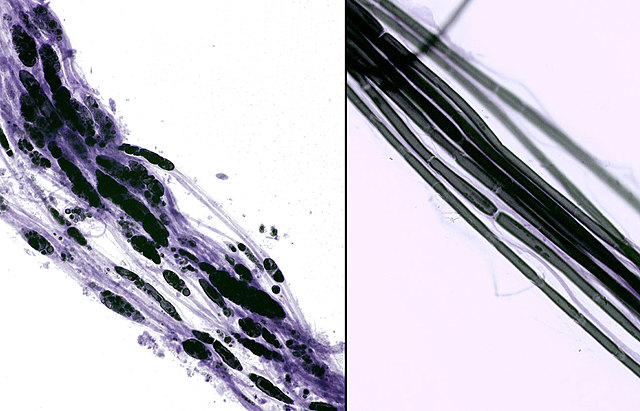

• Método de tintura con croato de plata

Método de tintura con croato de plata

• Camillo Golgi (1843-1926)

• Utilizó este método para el estudio de tejidos nerviosos y así identificó una clase de células dotadas con extensiones (dentritas), mediante las cuales se conectan con otras células nerviosas. Estos descubrimientos luego serían de gran utilidad para otros científicos (Wilhelm Bon Waldeyer-Hartz o Ramón y Cajal)